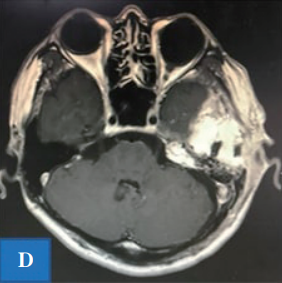

D:术后磁共振成像。